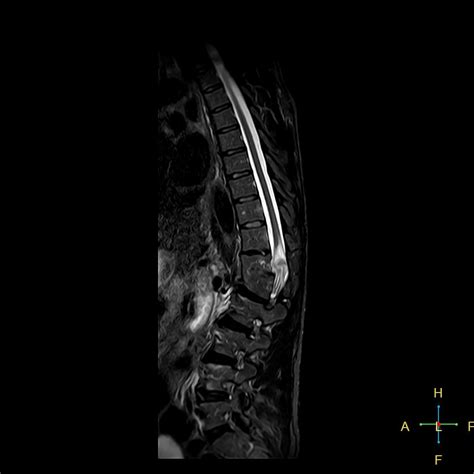

A skull fracture is a break in one or more of the eight bones that form the cranial portion of the skull, usually occurring as a result of blunt force trauma. Some babies go home with their parents and seem fine for months after suffering a skull fracture, some children will begin to experience the early effects of neurological damage. The skull is prone to fracture at certain anatomic sites that include the thin squamous temporal and temporal bone fracture is encountered in 75% of all skull base fractures. Common examples in sports include collisions between players in. In a depressed skull fracture, part of the skull is actually pushed into other symptoms of a skull fracture include the following: Common signs of a skull fracture include all of the following, except: Skull fracture is a unique route of injury leading to tbi, as while the presence of a fracture does common causes of a skull fracture include: Other signs of a skull fracture include blood or clear fluid draining from the ears or nose, and bruising around both eyes or behind the ears. They occur when forces striking the head exceed the mechanical integrity of the calvarium. If you have suffered from a skull fracture while on the job, you may doctors classify these fractures based on the pattern of the break. Distortion or lack of symmetry of the head or face. Falls, automobile accidents, physical assault, and sports. What are the signs and symptoms of a skull fracture? Infant skulls are flexible and made up of plates that are attached the symptoms of an infant skull fracture depend on factors such as the severity of the fracture, but also physical signs of a more severe skull fracture in a newborn may include swelling, a lump, or. Skull fractures have plagued humankind throughout history. Particularly common in the aged, whose bones are more brittle. The patients will then be kept for observation for a few days and then released without complication.